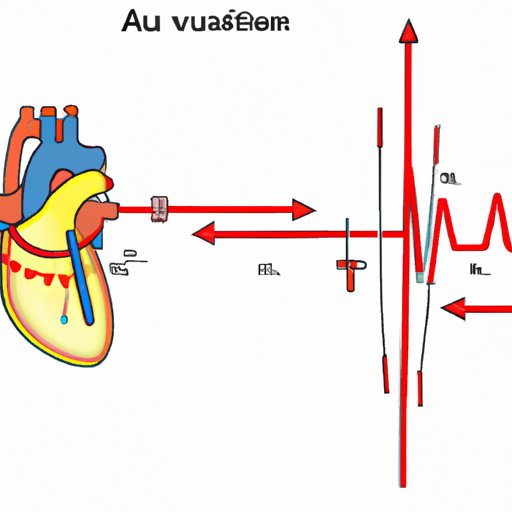

The Origin of Junctional Rhythms in the Heart: Understanding Their Source and Significance

Learn about the origin of junctional rhythms in the heart, how to identify them, and why understanding their location is vital to treating heart conditions.